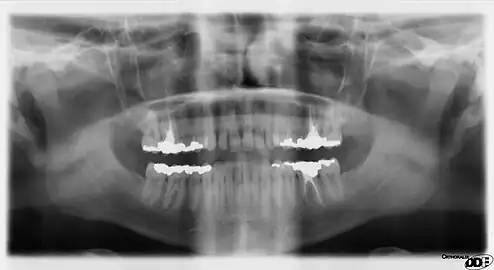

Panoramic films

Panoramic films are extraoral films, in which the film is exposed while outside the patient's mouth, and they were developed by the United States Army as a quick way to get an overall view of a soldier's oral health. Exposing eighteen films per soldier was very time consuming, and it was felt that a single panoramic film could speed up the process of examining and assessing the dental health of the soldiers; as soldiers with toothache were incapacitated from duty. It was later discovered that while panoramic films can prove very useful in detecting and localizing mandibular fractures and other pathologic entities of the mandible, they were not very good at assessing periodontal bone loss or tooth decay.[18]